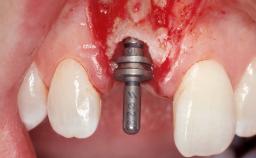

A 30-year-old female patient had lost tooth 21 and was referred to our clinic for consultation and treatment. Due to advanced apical infection, tooth 21 had been extracted two months earlier at another clinic and an acrylic-resin tooth had been bonded to the adjacent teeth. The patient desired implant treatment to avoid any damage to the adjacent natural teeth. While the patient had no history of any systemic disorder, she was a heavy smoker and exhibited medium to advanced periodontitis in the entire jaw. After the initial treatment to achieve a pocket probing depth of less than 4 mm and no bleeding on probing, a decrease in the height of the papillae mesial and distal to the extraction site and overall gingival recession were observed.

| Type of Implants | One-Piece|Reduced-Diameter |

| Bone Volume | Deficient horizontally, requiring prior grafting |